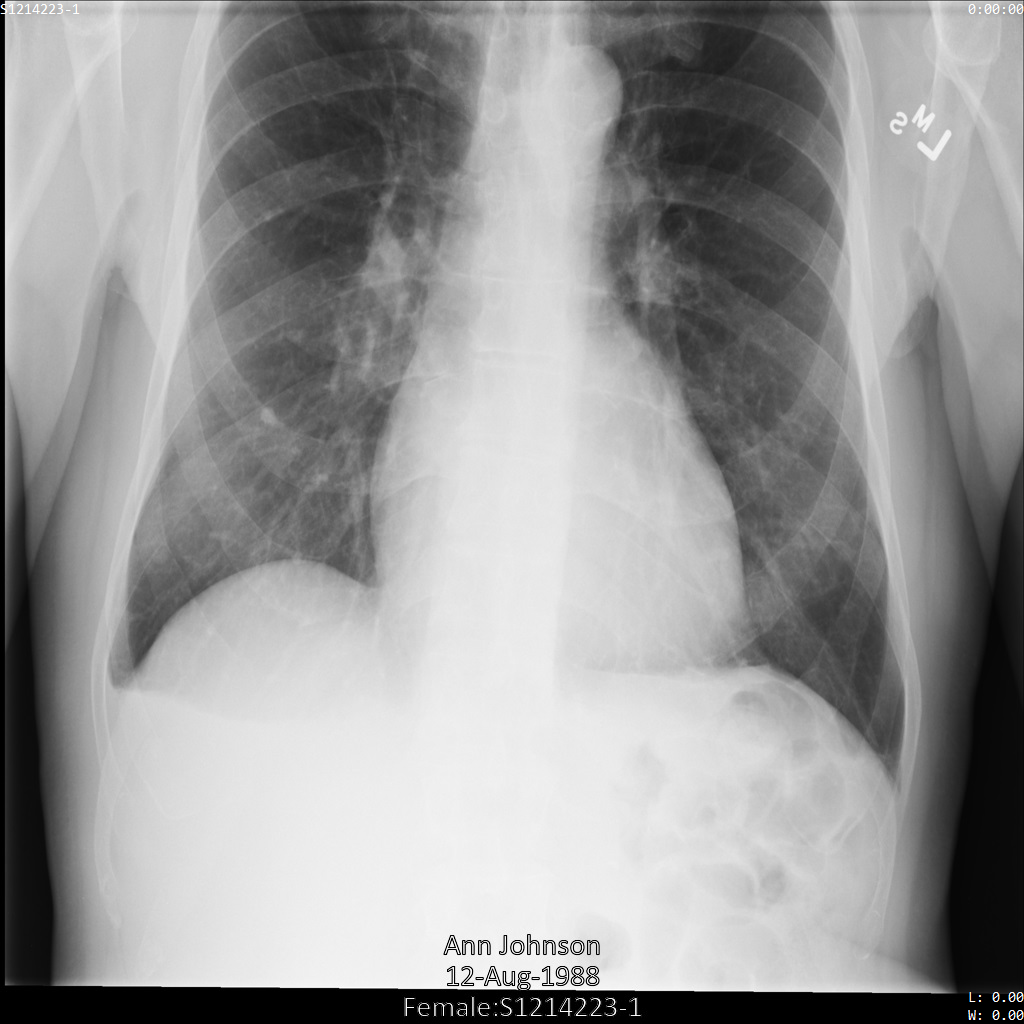

En cada una de las siguientes secciones, se proporcionan ejemplos de cómo desidentificar datos de DICOM mediante varios métodos. Se proporciona un resultado de la imagen desidentificada en cada muestra. En cada muestra, se usa la siguiente imagen original como su entrada:

Puedes comparar la imagen de salida de cada operación de desidentificación con esta imagen original para ver los efectos de la operación.

Después de enviar la imagen a la API de Cloud Healthcare, la imagen aparece de la siguiente manera. Mientras se ocultan los metadatos que se muestran en las esquinas superiores de la imagen, la información de salud protegida (PHI) quemado en la parte inferior de la imagen permanece. Para quitar también el texto quemado, consulta Oculta el texto quemado de las imágenes.